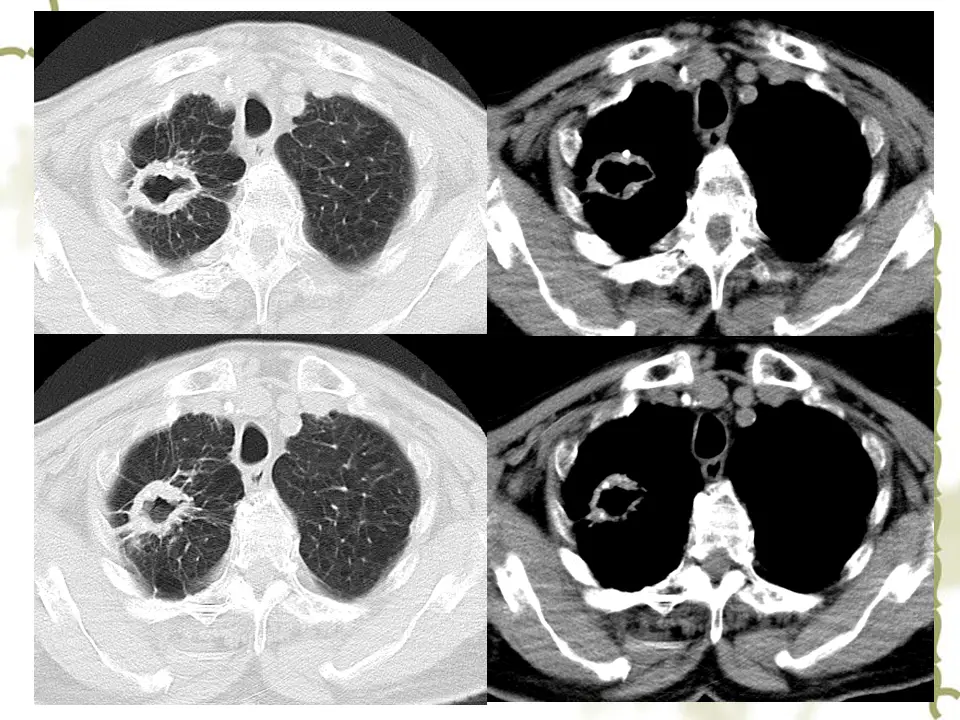

肺空洞是一种常见的疾病,它在肺部形成了一个孔洞。这个孔洞通常由于感染引起的肺组织坏死而形成。最常见的原因是结核菌感染,但也可能与其他细菌、真菌或寄生虫感染有关。当感染侵袭肺部时,免疫系统会试图清除感染,但有时会导致肺组织死亡,并形成空洞。

肺空洞的症状各异,包括持续咳嗽、咳出血痰、胸痛以及呼吸困难。然而,有些人可能没有任何明显的症状。要确诊肺空洞,医生通常会进行一系列检查,包括胸部X射线、CT扫描和支气管镜检查。这些检查可以帮助医生确定肺部是否存在空洞,并排除其他可能的疾病。